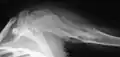

| X-ray image showing enchondromas localized in the lower part of the radius of a 7-year-old girl with Ollier disease. | |

X-ray showing enchondromas localized in the lower part of the radius of a 37-year-old patient affected with Ollier disease -